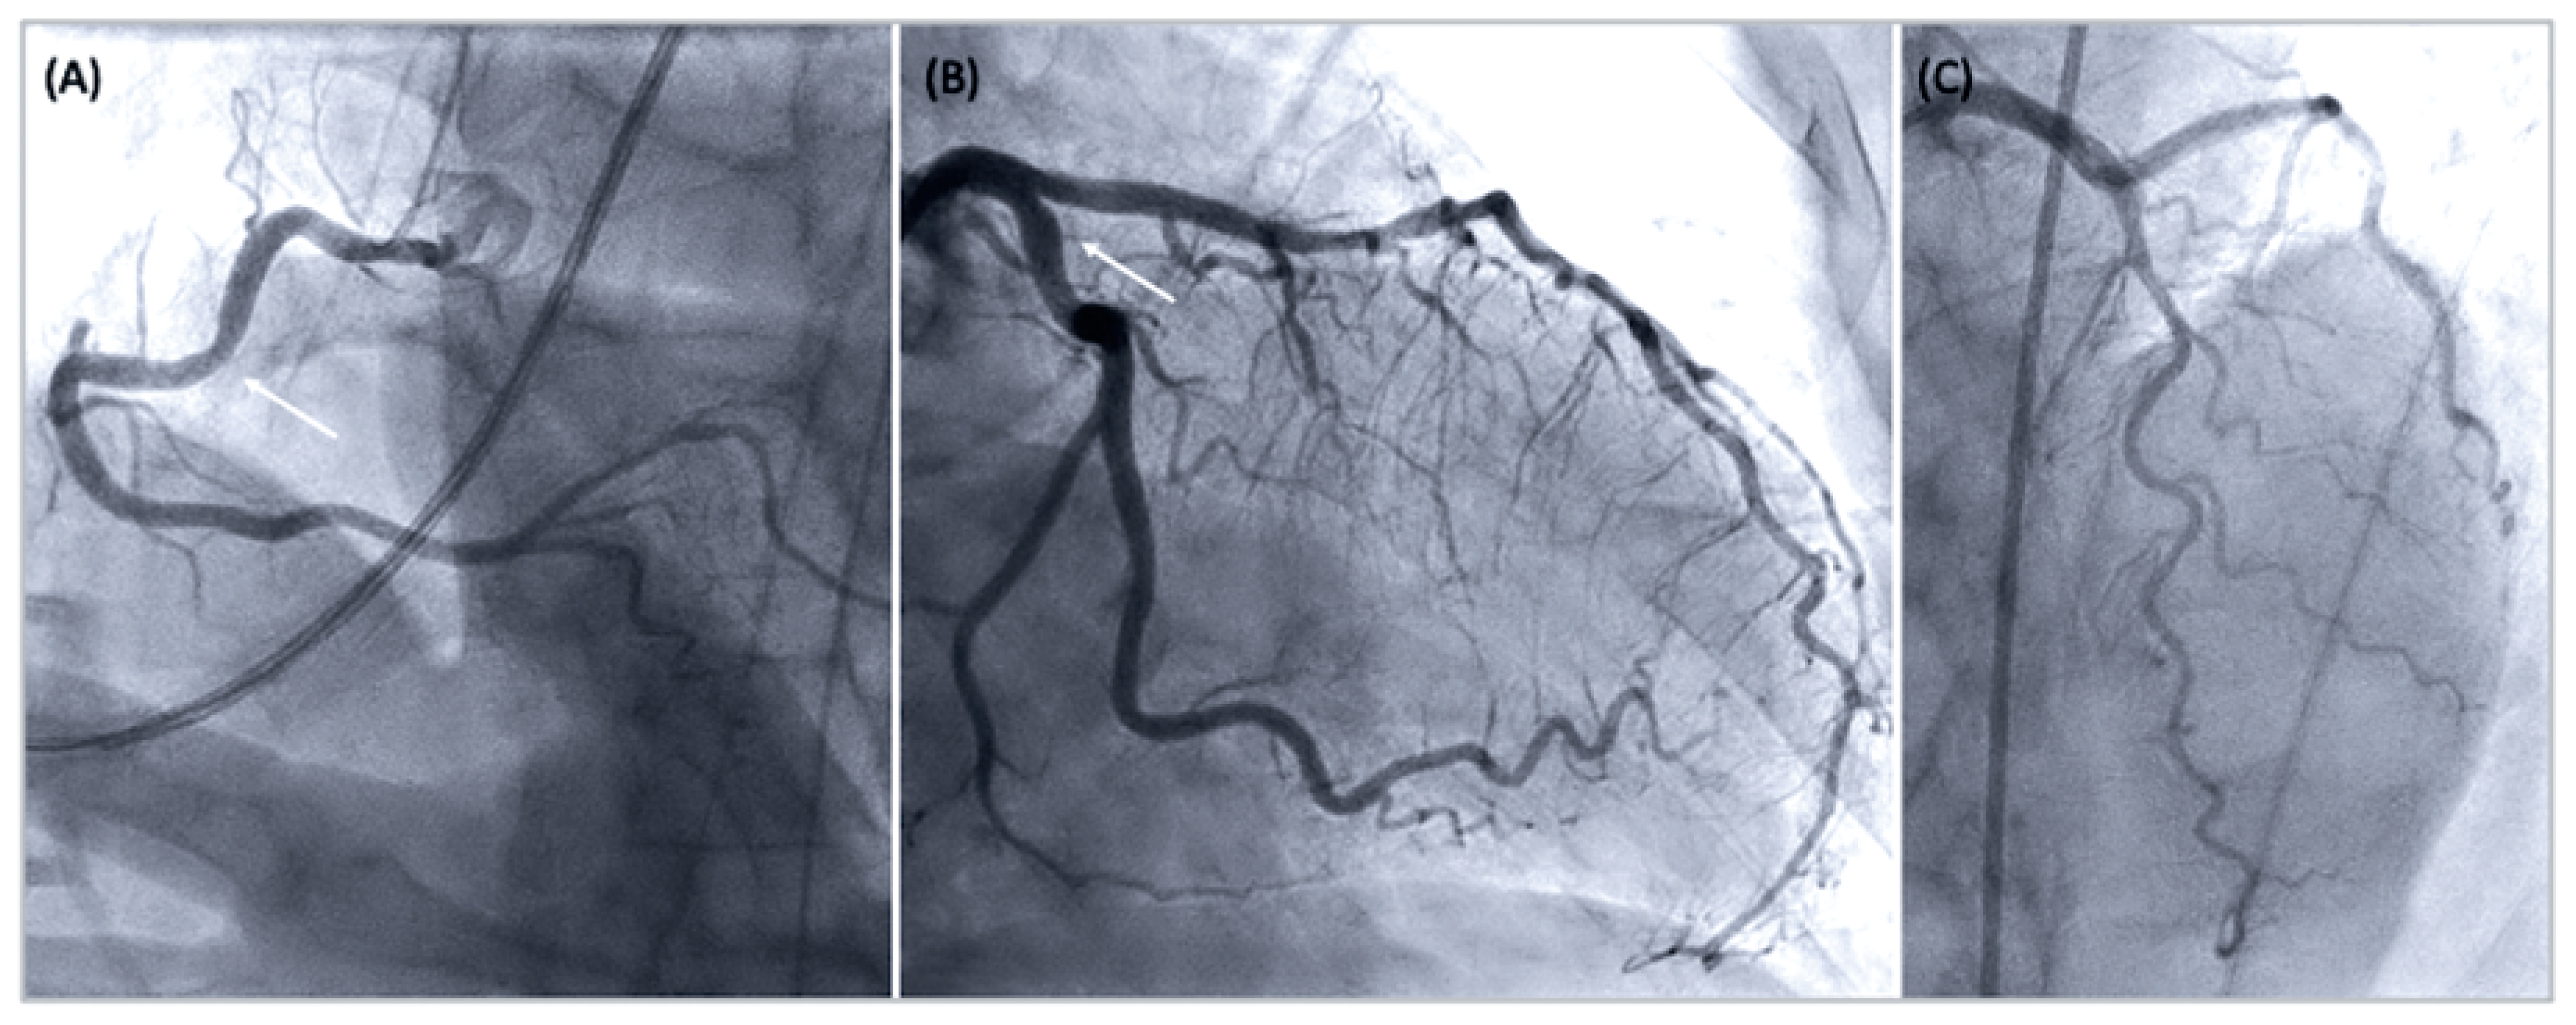

| Documentation of coronary artery spasm (>90% constriction) during coronary angiography, spontaneously or in response to a provocative stimulus (typically acetylcholine, ergotamine, or hyperventilation); accompanying transient angina and ischaemic ECG changes (as above). |